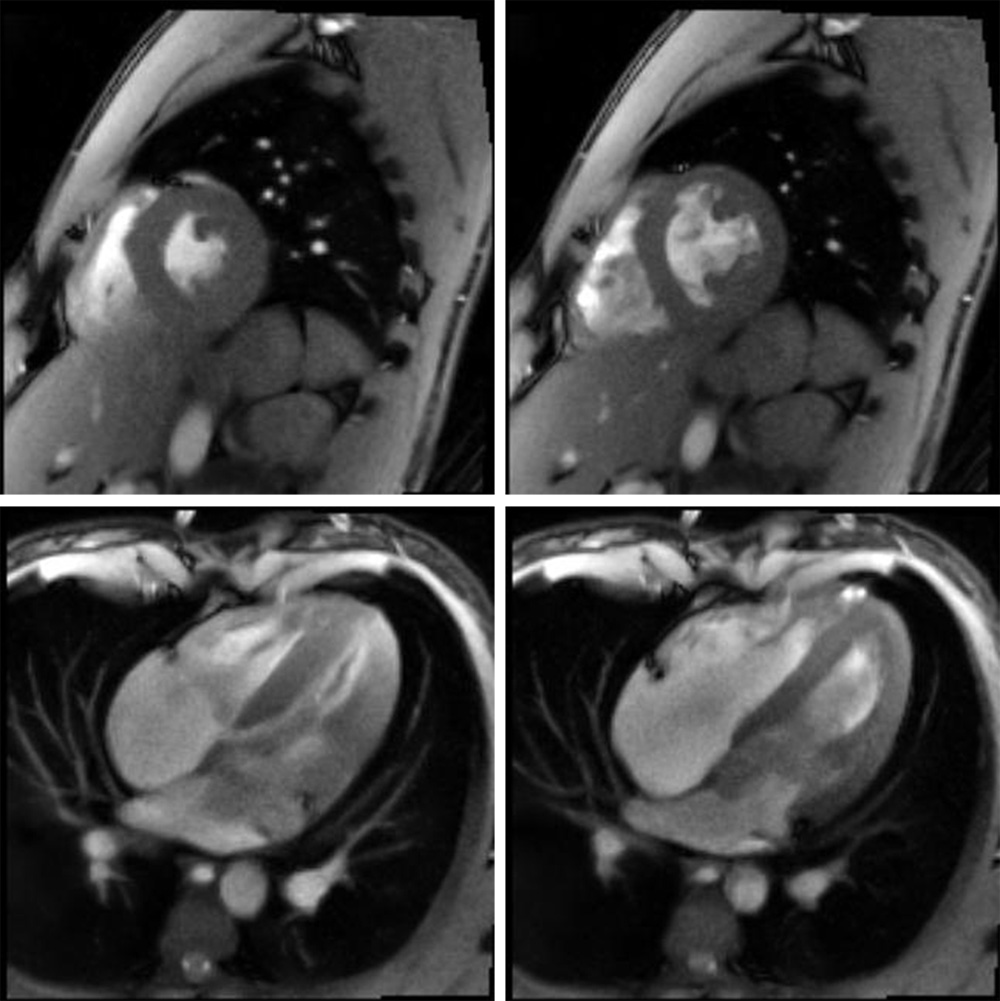

In 2010, Frahm and his team achieved another breakthrough by also solving the problem of the high number of individual measurements required: With FLASH 2 they presented a further innovation that uses a new mathematical method for image reconstruction and thus needs only a very small number of individual measurements per image. This method significantly accelerates the MRI imaging even further. The measurement time per image can thereby be reduced to one hundredth of a second. For the first time, it is therefore now possible to make real-time recordings from inside the body and observe joint movements, speech movements, swallowing processes or the beating heart “live”. It is also possible to use MRI to examine patients whose condition leaves them unable to hold their breath for a longer period. In addition, the new technique could also be used in the future to accompany minimally invasive surgery and treatments, which are currently being conducted under X-ray control.

Human heart: on the left a systolic contraction phase and on the right a diastolic expansion phase; above a short-axis view below a 4-chamber view with 33 ms resolution (© MPI for Biophysical Chemistry) -